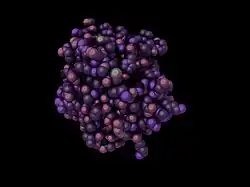

indolethylamine N-methyltransferase (with slight variation on CPK coloration) – See PDB 2A14 | |||||||||

As of late 2007, only one structure has been solved for this class of enzymes, with the PDB accession code 2A14.